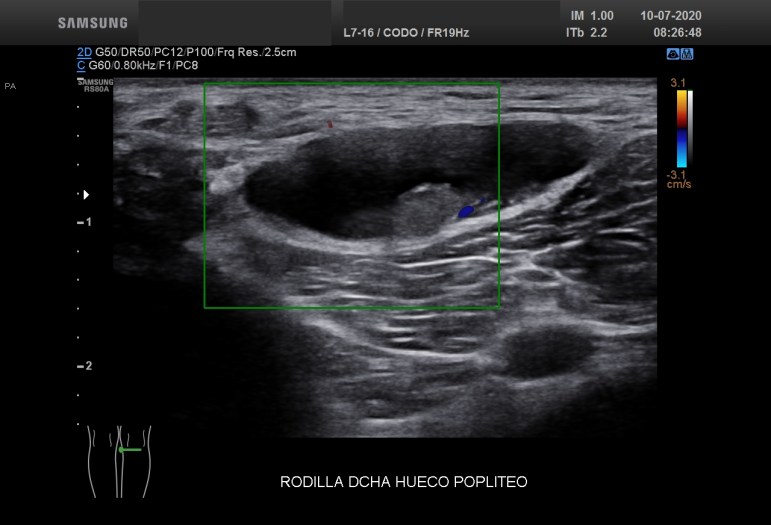

Recuerdo la importancia de comprobar siempre la permeabilidad de los vasos del hueco poplíteo con este tipo de patologías, el parecido de los síntomas de un quiste de Baker roto y la TVP puede ser muy similar y sin embargo, la TVP es una patología potencialmente peligrosa. Para ello pide al paciente que suba la pierna afectada por encima de su otra pierna para poder hacer que el retorno venoso sea más evidente y poder estudiar los mencionados vasos, sobre todo, su vena, claro.

La compresión con la sonda del hueco poplíteo establece la permeabilidad de la vena poplitea. Normalidad por tanto, manda, el comportamiento de la vena, compresible, y no el uso del doppler, por eso me permito el lujo de enseñarte la técnica sin el uso del doppler color. Línea roja: Si la vena no se colapsa.